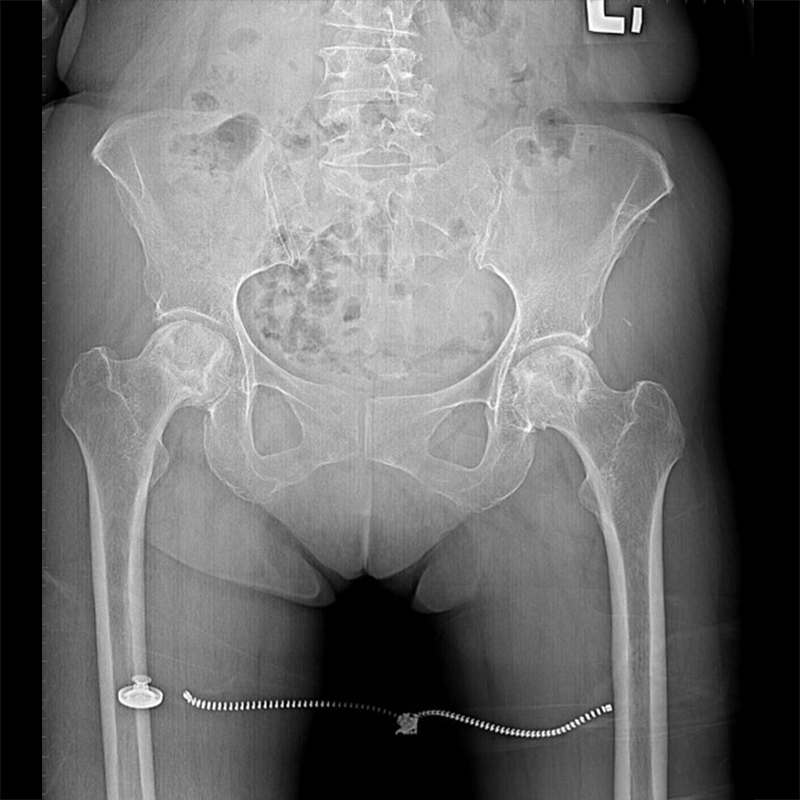

傳統髖關節置換 首頁 案例分享 髖關節手術 傳統髖關節置換 54歲蔡先生退化性關節炎 術前 術後 張女士 51歲 退化性關節炎(DDH先天發育不全 CROWE TYPE 2) 術前 術後 38歲林先生 退化性關節炎 術前 術後 72歲謝女士 退化性關節炎 術前 術後 71歲 謬女士 骨股頭壞死 術前 術後 50歲 郭先生骨股頭壞死 術前 術後 80歲 盧先生骨股頭壞死 術前 術後 林先生 37歲 術前 術後 邱女士 51歲 術前 術後 張女士 50歲 術前 術後